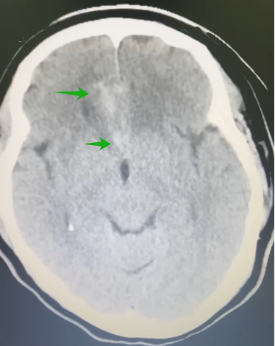

近期我神经外科二区收治一例颅脑损伤超40多天,反复头痛不缓解,经检查发现外伤导致颅内假性动脉瘤的病例。患者陈某某,女,49岁,40多天前因为车祸伤,在当地医院住院治疗,当地医院诊断:蛛网膜下腔出血,经治疗后头痛好转,但1天前头痛症状又再次加重,伴呕吐,复查头颅CT发现右额叶脑出血,从当地人民医院转至我院神经外科。检查患者身体状况:神志清,视力视野正常,颈软无抵抗,四肢肌力V级,肌张力正常。

▲CT示病灶扩大、出血